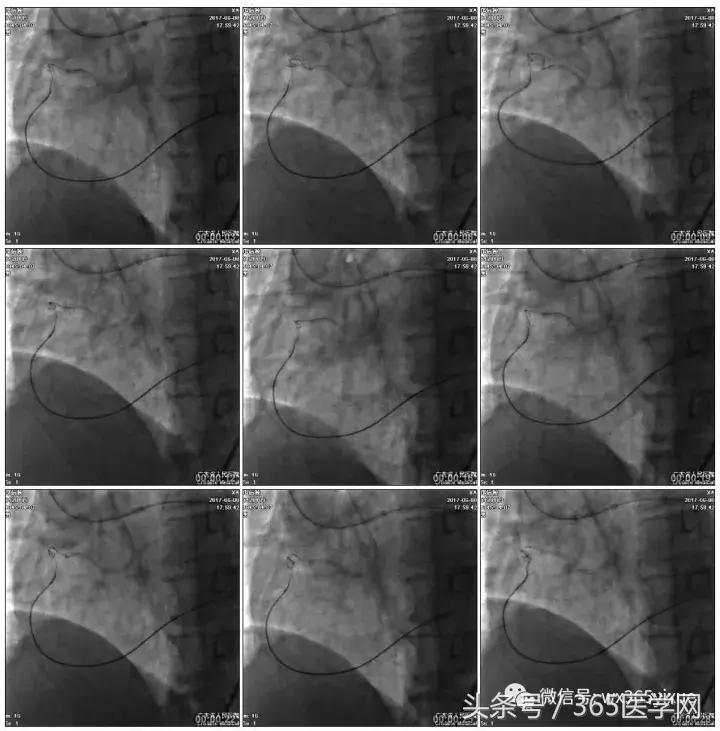

第二步:处理LCX

Fielder XT-A,Gaia First ---在微导管支撑下通过闭塞病变

LCX植入支架

2.0*10mm球囊

2.75*22mm药物支架